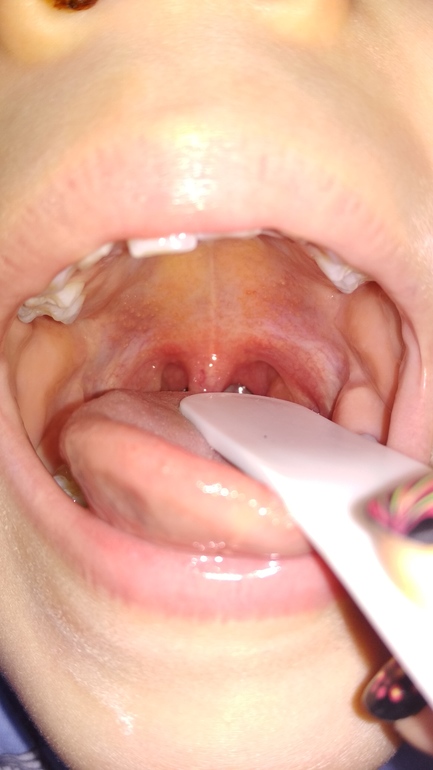

3. Проходили неделю в сад и 12 мая опять Ярик сказал, что глотать больно (фото прикладываю, там где сыпь на нёбе как прыщики, фото с белым шпателем), темп со второго дня 37-37.4. По виду - как было при скарлатине только без сыпи по телу. Никаких анализов пока не сдали. Больно глотать слюни уже 3 дня. Пьем иммудон, фарингосепт, в нос физраствор-полидекса-проторгол, эриус и синупрет.